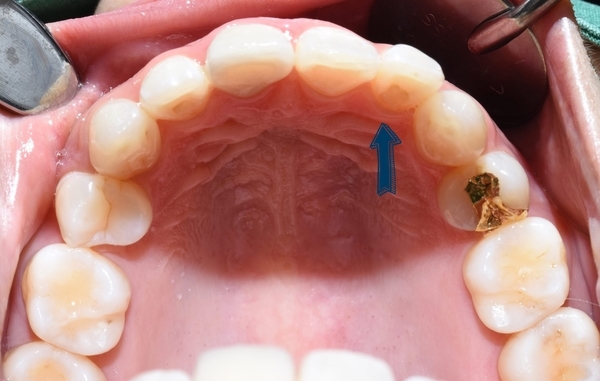

이번 소개해 드릴 분은 몇 년 전 다른 치과에서 교정을 하셨는데

다시 앞니가 튀어나와보인다는 것을 해결하기 위해 오신 환자분입니다.

많이 튀어나오진 않았지만, 유독 이런 이가 사진을 찍을 때 도드라지게 보이죠.

사진에서 한 치아가 옆 치아들과 비교해 유독 튀어나온 것 같은 느낌? 있으시죠?

이렇게 말이죠. 위 사진의 환자분의 아래쪽 치아입니다.